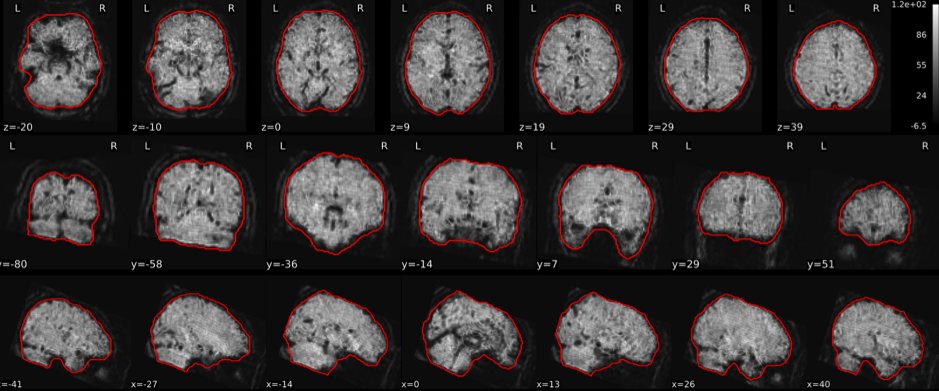

EPI tSNR

In the signal to noise ratio images of the resting state image the desired signal is compared to the amount of background noise. It is important to check all the views (sagittal, coronal, axial) because some artefacts (e.g., stripes) may be evident only in one particular view.

Example of a good subject

- Signal to noise is symmetrically distributed and there is no signal distortion

Example of a bad subject

- Asymmetry

- Potential signal distortion (might represent an artefact)

- Signal drop-out

- Stripes artefact

Clear large artefact (e.g., zebra stripes in example 1) are worth the exclusion of the subject. If you are unsure, check the other quality metrics for that subject to decide whether they should be excluded.

Summary

| good | bad |

|---|---|

| Symmetrical distribution of noise and signal | Asymmetry |

| No disruptions of the signal (no “black patches”) |

Potential signal disruptions (could be related to artefacts) |

| No stripes (sign of high motion) |

Signal drop |

| Stripe artefacts (“zebra” stripes due to motion) |